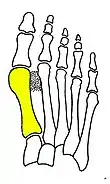

- For recurrence correction after osteotomy procedure (Fig. 8)

Late deformity recurrence can happen after osteotomy (bone-breaking) procedures because osteotomy surgeries do not specifically stabilize first metatarsal bone.